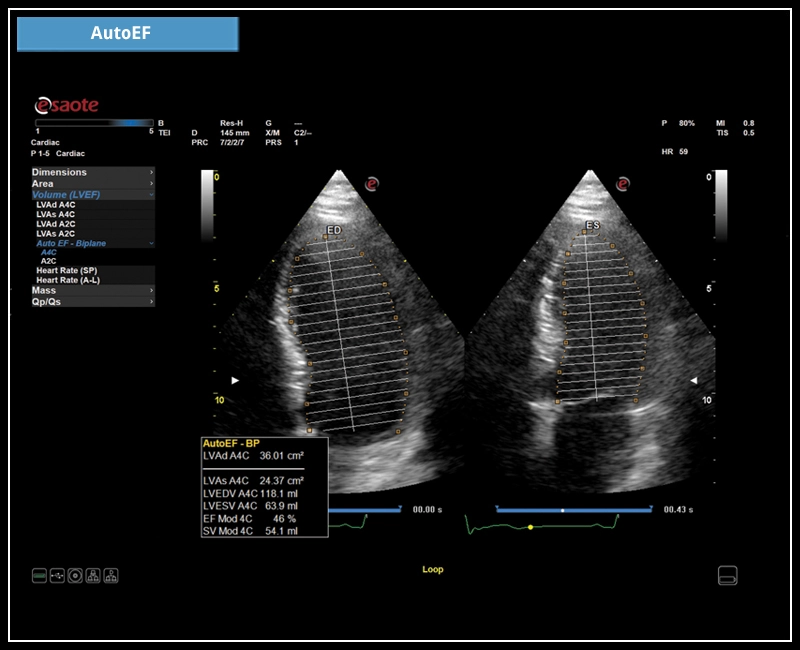

MyLab™E80 - AutoEF

MyLab™E80 - AutoEF

MyLab™X90 - AutoEF Automatic Ejection fraction assessment of the left ventricle

MyLab™X90 - AutoEF Automatic Ejection fraction assessment of the left ventricle